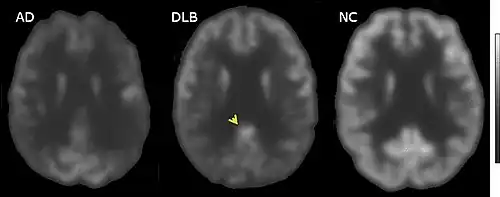

Direct laboratory-measurable biomarkers for DLB diagnosis are not known, but several indirect methods can lend further evidence for diagnosis.[24] The indicative diagnostic biomarkers are: reduced dopamine transporter uptake in the basal ganglia shown on PET or SPECT imaging; low uptake of 123iodine-metaiodobenzylguanidine (123I-MIBG) shown on myocardial scintigraphy; and loss of atonia during REM sleep evidenced on polysomnography. Supportive diagnostic biomarkers (from PET, SPECT, CT, or MRI brain imaging studies or EEG monitoring[121]) are: lack of damage to medial temporal lobe (damage is more likely in Alzheimer's disease[113]); reduced occipital activity; and prominent slow-wave activity on EEG.[24]

PET or SPECT imaging can be used to detect reduced dopamine transporter uptake and distinguish AD from DLB.[56][144] Severe atrophy of the hippocampus is more typical of AD than DLB.[145] Before dementia develops (during the mild cognitive impairment phase), MRI scans show normal hippocampal volume. After dementia develops, MRI shows more atrophy among individuals with AD, and a slower reduction in volume over time among people with DLB than those with AD.[32] Compared to people with AD, FDG-PET brain scans in people with DLB often show a cingulate island sign.[32]